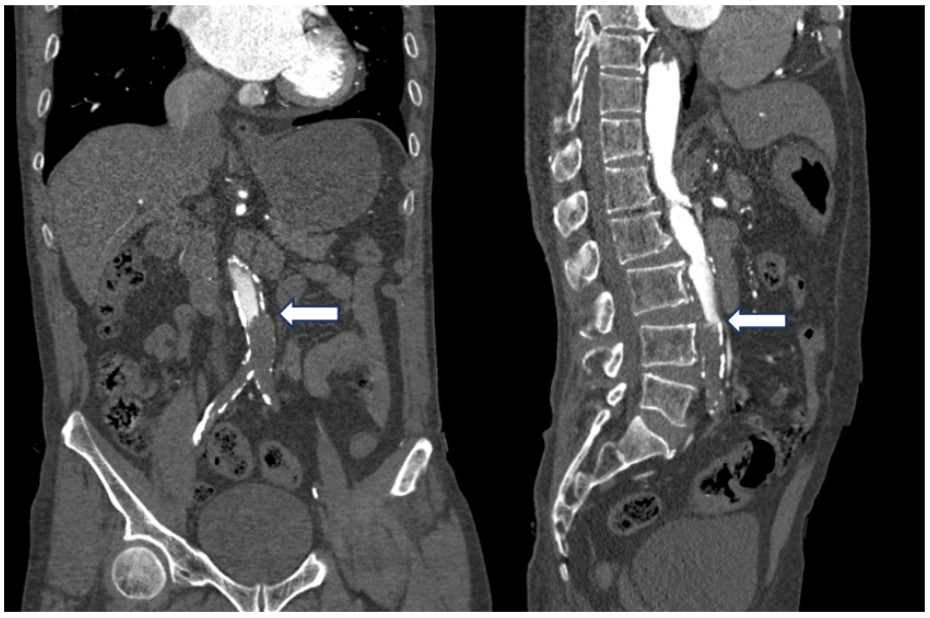

既往史:有高血压病史10年余,规律降压治疗,未监测血压。房颤病史2年余,2022年11月在本院超声心动图显示左心房见一不均质低回声团,位置随心动周期漂动(17 mm×16 mm)”(见图 1),左房前后径40 mm,左右径46 mm,上下径70 mm。LVEDD 39 mm,LVEF:60%。二尖瓣E峰0.92 m/s,最大压差3.39 mmHg(1 mmHg=0.133 kPa)。反流面积3.8 cm2,二尖瓣口频谱呈单峰。舒张期二尖瓣口前向血流,E < A,无舒张功能不全。进一步行经心脏超声造影提示:Flash后,左心室心腔内团块未见明显灌注(见图 2)。

| 注:Flash后,左心室心腔内团块影(箭头处)未见明显灌注 图 2 经患者肘静脉注射造影剂“声诺维”后行心脏超声造影(左心声学及心肌灌注) |